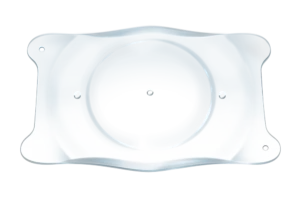

- Collamer is een poly-HEMA-gebaseerd copolymeer met een UV-absorberende chromofoor die UV-bescherming biedt.

STAAR’s exclusieve, premium Collamer®-materiaal

Collamer heeft een bewezen geschiedenis van meer dan 20 jaar met meer dan 3 miljoen ICL-lenzen wereldwijd verspreid. Het is een copolymeer van poly-HEMA en collageen, dat UV-bescherming biedt. Collamer minimaliseert bovendien:

- Ontsteking

- Flare

- Cellulaire reacties8,9